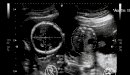

يمثل الشهر السابع من الحمل بداية الثلث الثالث أو المرحلة الأخيرة من الحمل، ويبدأ من الأسبوع السابع والعشرين حتى الأسبوع الثلاثين، وخلال هذه الفترة يستمر نمو أعضاء وأجهزة الجنين، ويزداد طوله ووزنه كدليل على نموه بشكل صحي وسليم داخل الرحم، وخلال هذا الشهر يكتسب الجنين الوزن بشكل سريع؛ حيث يبلغ وزنه حوالي كيلوغرام في بداية الشهر ويصل إلى حوالي 1800 غرام في نهايته.